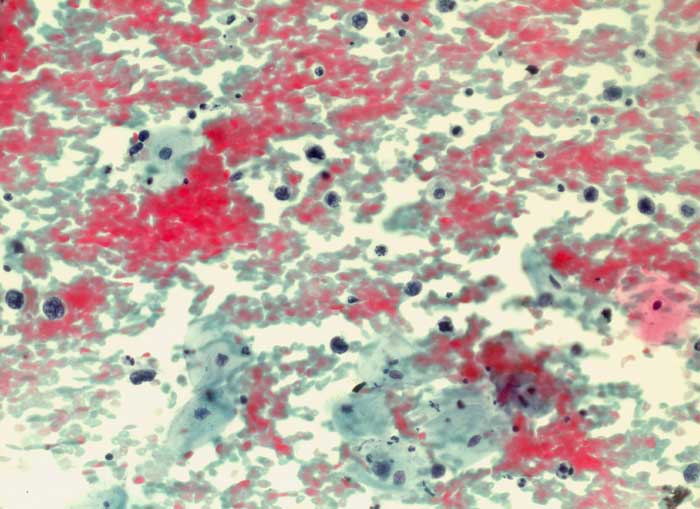

PathoPic ID 6270 - diffuses grosszelliges B-Zelllymphom

diffuses grosszelliges B-Zelllymphom

maligner Tumor

Portio

Genitalorgane, weiblich

Portioabstrich: Auf blutigem Hintergrund einzeln liegende nacktkernige

Lymphomzellen und

Apoptosen. Zellverbände oder organoide Strukturen fehlen. Ausserdem sieht man

Plattenepithelien vom intermediären und superfizialen Zelltyp.

Autopsie: Generalisiertes diffuses grosszelliges B-Zell Lymphom

St.n. Non Hodgkin-Lymphom. Rezidiv iliacal rechts.

Zytologische Diagnose: Hochgradig atypische lymphoide Elemente. Befund vereinbar mit malignem grosszelligem Lymphom.